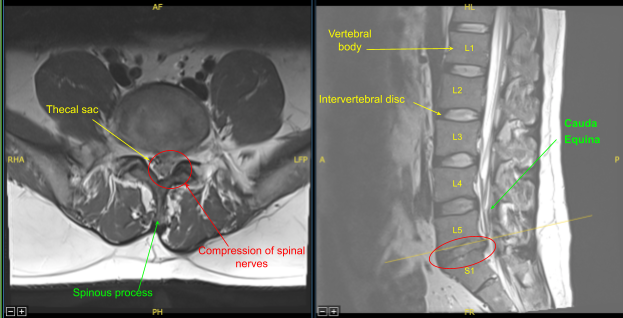

Magnetic resonance imaging (MRI) was done, which showed previous left hemilaminectomy at L5-S1, Left central disc herniation/extrusion at L5-S1 contributes to effacement of the thecal sac and left lateral recess with severe spinal canal stenosis and mass effect upon the descending left S1 and at least S2 nerve roots.